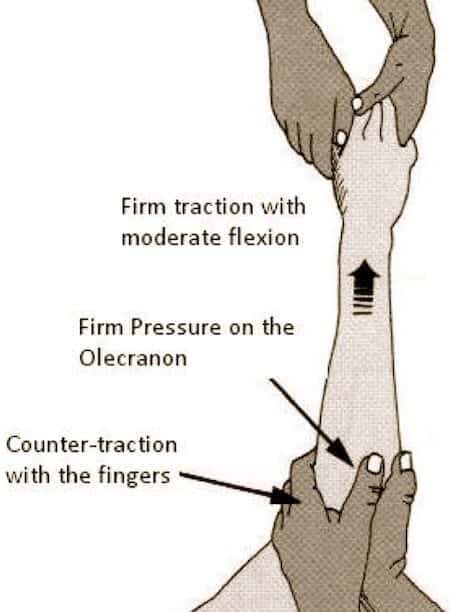

If this is performed externally, that is, without opening the arm, it is known as closed.

Caution can help reduce your risk of a dislocated elbow. The act of restoring alignment to the elbow is called a reduction maneuver. Types of reduction of elbow dislocation first aid immediately after the injury you should put.

Listen for a click or a palpable pop at the radial head, which. A gentle pull and push and the elbow could be back in place. Often, in addition to a dislocation, there is a fracture with displacement of bone fragments, etc.

Inject 3 to 5 ml of anesthetic. Read customer reviews & find best sellers. Avoid overtraining in sports to avoid overuse injuries.